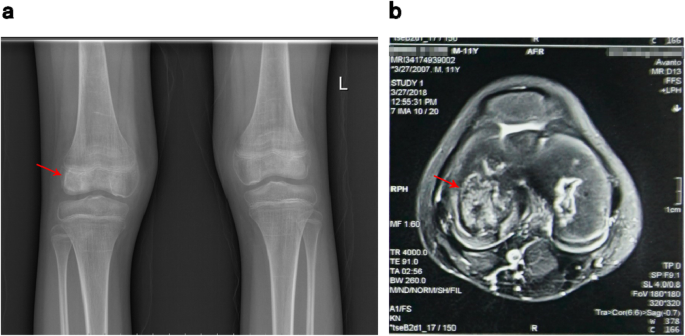

Wang, a 6-year-old boy, was hospitalized with “a week of limb aches after activities” in 2013, and was comprehensively diagnosed with “aplastic anemia” and then treated with cyclosporine (50 mg, bid). After genetic compatibility test, he was found to match his sister’s human leukocyte antigen (HLA) 10/10, so the allogeneic hematopoietic stem cell transplantation was successfully performed on June 2nd, 2016 (9 years old). The implantation rate was examined to be 85 % using fluorescence in situ hybridization (FISH) at 3 months after transplantation. He began to take methylprednisolone tablets (12 mg, bid), cyclosporin tablets (75 mg, bid) and mycophenolate mofetil tablets (250 mg, bid) after transplantation. Methylprednisolone tablets started to decrease after maintaining the dose for about half a year. In January 2017, the dosage of methylprednisolone tablets was reduced to 8 mg, bid, and then 4 mg, bid in February, and stopped in March. He persistently took cyclosporine (75 mg, bid) and mycophenolate mofetil tablets (250 mg, qd) since the transplantation. He didn’t take tacrolimus capsules (2.5 mg, tid), sirolimus tablets (1 mg, qd) and calcium carbonate D3 (1 tablet, qd) until rejection occurred in November 2017. In January 2018, he was diagnosed with “keratitis” due to photophobia and hyperemia in his left eye without obvious cause. Cytomegalovirus viral load DNA copy number was tested and in normal range (< 500 IU/ml). He received the therapy of ganciclovir (150 mg, bid), methylprednisolone (2 mg, bid) and cyclosporine (25 mg, qd) for the consideration of viral infection and chronic graft versus host disease (GVHD) after transplantation. Three months later, due to the pain and discomfort of both hips, he underwent bilateral hip X-ray and magnetic resonance examinations at the local hospital, which showed bilateral necrosis of the femoral osteoepiphysis (Fig. 1).

Subsequently, he was hospitalized again with “keratitis”, “aplastic anemia after hematopoietic stem cell transplantation”, and “bilateral necrosis of the femoral osteoepiphysis”. During his stay in the hospital, the drug concentrations of cyclosporine were monitored as CsA 175.00ng/ml and CsA 102.10ng/ml respectively on April 3rd and 9th, 2018, which normal level ranges from 100 to 200ng/ml. After admission to the hospital, ganciclovir (150 mg, bid), methylprednisolone (2 mg, bid) and cyclosporine (75 mg, bid) were given to alleviate graft-versus-host reaction, and then his visual acuity gradually improved. Methylprednisolone was discontinued after one month, and he was discharged on April 29th after his condition improved. After discharge, he continued taking the post-transplant medication. On May 22nd, he was hospitalized again with “two days of sore throat” with a large area of ulcer in his oral cavity. After treated with rituximab (5 mg, qw, 4 times in total), he continued to receive ganciclovir (150 mg, bid) antiviral treatment, and then his oral ulcers gradually improved. On May 26th, He developed the symptom of macroscopic hematuria, and urine routine examination showed positive urinary protein (1+) and positive urine occult blood (3+), while other indexes were normal. Blood analysis was reviewed on May 28th, and tacrolimus drug concentration was monitored as FK 506 11.60ng/ml (normal range: 5-10ng/ml), and sirolimus dose was adjusted at the same time of excluding infection. Blood routine test was reviewed on June 3rd, and he was treated with rituximab again. The treatment went on smoothly and the symptom of macroscopic hematuria was better than before. He was discharged on June 4th and continued to take the post-transplant medication. After discharge, he still felt painful in joints and could not walk easily. Worried about the deterioration of his condition, he was hospitalized in the First Affiliated Hospital of Guangzhou University of Chinese Medicine on June 19th. He complained of pain in movements of the hips, knees and ankles at admission, which was relieved after rest. After physical examination, he was found to have the following signs: multiple pigmentation spots throughout the body, keratitis, declining vision, softening of nails and toenails, limited rotation of both hips, double knee joint internal and external roll test (+), limited dorsal extension of ankle joints (Fig. 2). X-ray examinations of the shoulders, hips, knees and ankles and magnetic resonance examinations of the shoulders, knees and ankles were performed subsequently (Figs. 3 and 4), indicating epiphyseal necrosis of bilateral humeral heads and femoral heads, talus osteonecrosis, and femoral condyle bone infarction. Suffering from the disease at the age of 9, the 11-year-old child’s weight is stable at about 30 kg now, which is in line with the normal weight, indicating that there is no overweight and malnutrition for him. Since his transplantation in 2016, he began to take a large amount of glucocorticoids and anti-rejection drugs for a long period of time. During the past two years, every time the child took glucocorticoids, he was accompanied by pain in the hips, knees and ankles, which was relieved after the drug withdrawal. According to the analysis of his concrete condition, it is suspected that there could be a certain timeliness between necrosis of the femoral head and taking large doses of glucocorticoids (see Table 1).

Although increasing studies on the etiology or pathogenesis of Perthes disease have been performed for the past several decades, the causes of Perthes disease still remain unclear. In this case, with MRI examination finding the epiphyseal necrosis of right humeral head, femur and tibia, and X-ray examination finding bilateral femoral head necrosis, the child was diagnosed as Perthes disease based on his clinical and imaging data. And we suppose that long-term and high-dose glucocorticoids may be one of the causes of Perthes disease. It is generally recognized that excessive glucocorticoids can cause femoral head necrosis in adults, but regarding the use of glucocorticoids causing Perthes Disease, this case report may be the first to put forward this view. The child in this case can be diagnosed as Perthes Disease, but further discussion is needed about/on whether it is caused by drugs, especially glucocorticoids. Through the analysis of the following aspects, it could be concluded that the main cause of Perthes disease for the child in this case is the long-term and high-dose use of glucocorticoids.